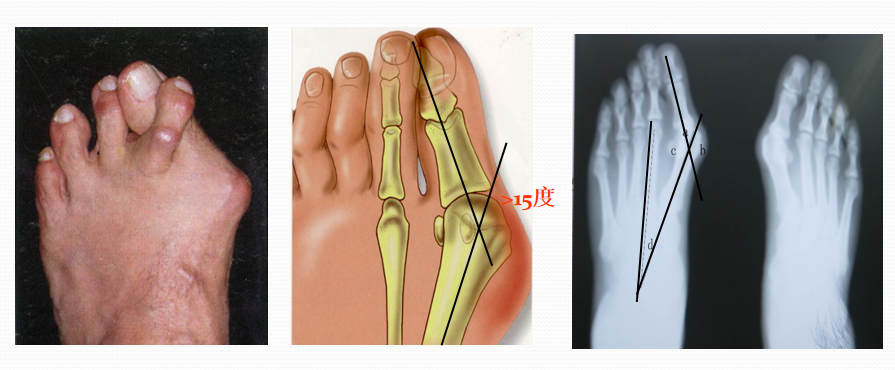

拇外翻也叫大脚骨病,是指拇趾向外偏斜超过正常生理角度的一种足部畸形,是目前最常见的足病之一。一般认为拇趾的外翻角>15º可诊断为拇外翻。

A为正常,B图中拇外翻角约15°,C、D、E的拇外翻角以15°递增。

但一部分人拇趾外翻虽然超过此角度而没有症状,而另一部分人拇趾外翻角度虽然不到15°,却有拇囊部位的疼痛。

1:前后位观察和测量拇外翻角(HAA)  :拇趾跖骨中轴线与近节趾骨中轴线之夹角。正常为15°~20°

第1、2跖骨间夹角(IMA):  第1、2跖骨中轴线之夹角。正常为9 °拇外翻时此角通常大于正常。